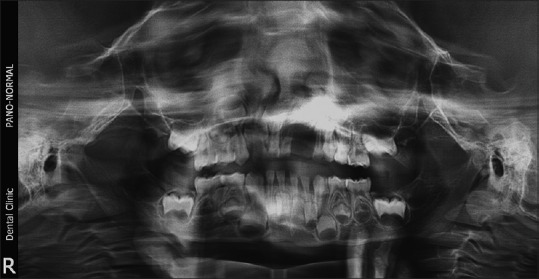

This case series comprises 5 GCG in children between the ages of 4 and 12 years. A retrospective analysis was conducted of all patients who were diagnosed with GCG and treated over 10 years (from August 2004 to August 2014) at Subharti Dental College and Hospital, Meerut, India. The lesions in these children were diagnosed and managed through interdisciplinary collaboration of the Departments of Oral and Maxillofacial Surgery, Oral Pathology and Microbiology and Pediatric Dentistry. Informed consent was obtained from the parents of all the children involved in the study. The analysis was approved by the Institutional Ethical Committee. The demographic details, clinical features, and management approaches of all the patients are listed in Table 1. Detailed history and clinical examination were performed for all the children. An orthopantomogram was taken for all the cases [Figures [Figures11 and and22].

| Figure 1:Preoperative orthopantomogram showing peripheral giant cell lesion in the left maxilla